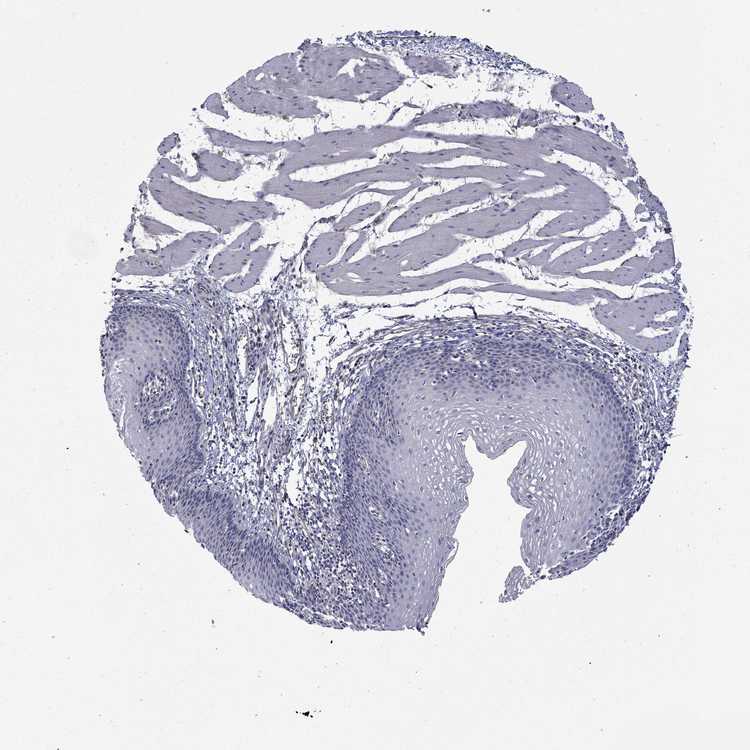

ESOPHAGUS - Antibody stainingi

Antibody staining in the annotated cell types in the current human tissue is reported as not detected, low, medium, or high, based on conventional immunohistochemistry profiling in selected tissues. This score is based on the combination of the staining intensity and fraction of stained cells.

Each image is clickable and will lead to virtual microscopy that enables deeper exploration of all samples and also displays staining intensity scores, fraction scores and subcellular localization as well as patient and tissue information for each sample.

Antibody HPA017389Antibody HPA063713

Squamous epithelial cells HighNot detected